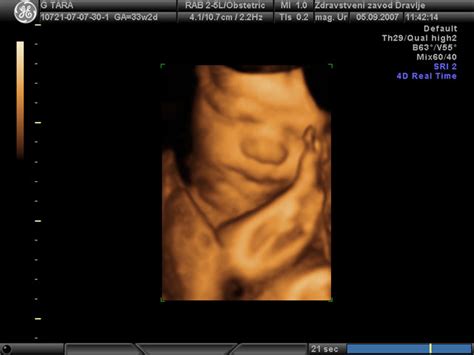

V 36. tednu nosečnosti je otrok že skoraj povsem razvit in opremljen z vsemi čutili. Nakopičil je maščobne zaloge, ki mu pomagajo pri uravnavanju telesne temperature po rojstvu, čeprav bo še vedno potreboval dodatno toploto. Vsi organi, vključno z možgani, delujejo ustrezno za življenje zunaj maternice. Otrok se je skoraj zagotovo že obrnil v porodni položaj z glavo navzdol. V primeru dvojčkov je položaj lahko nekoliko drugačen, saj se drugi otrok pogosto namesti ob prvega.